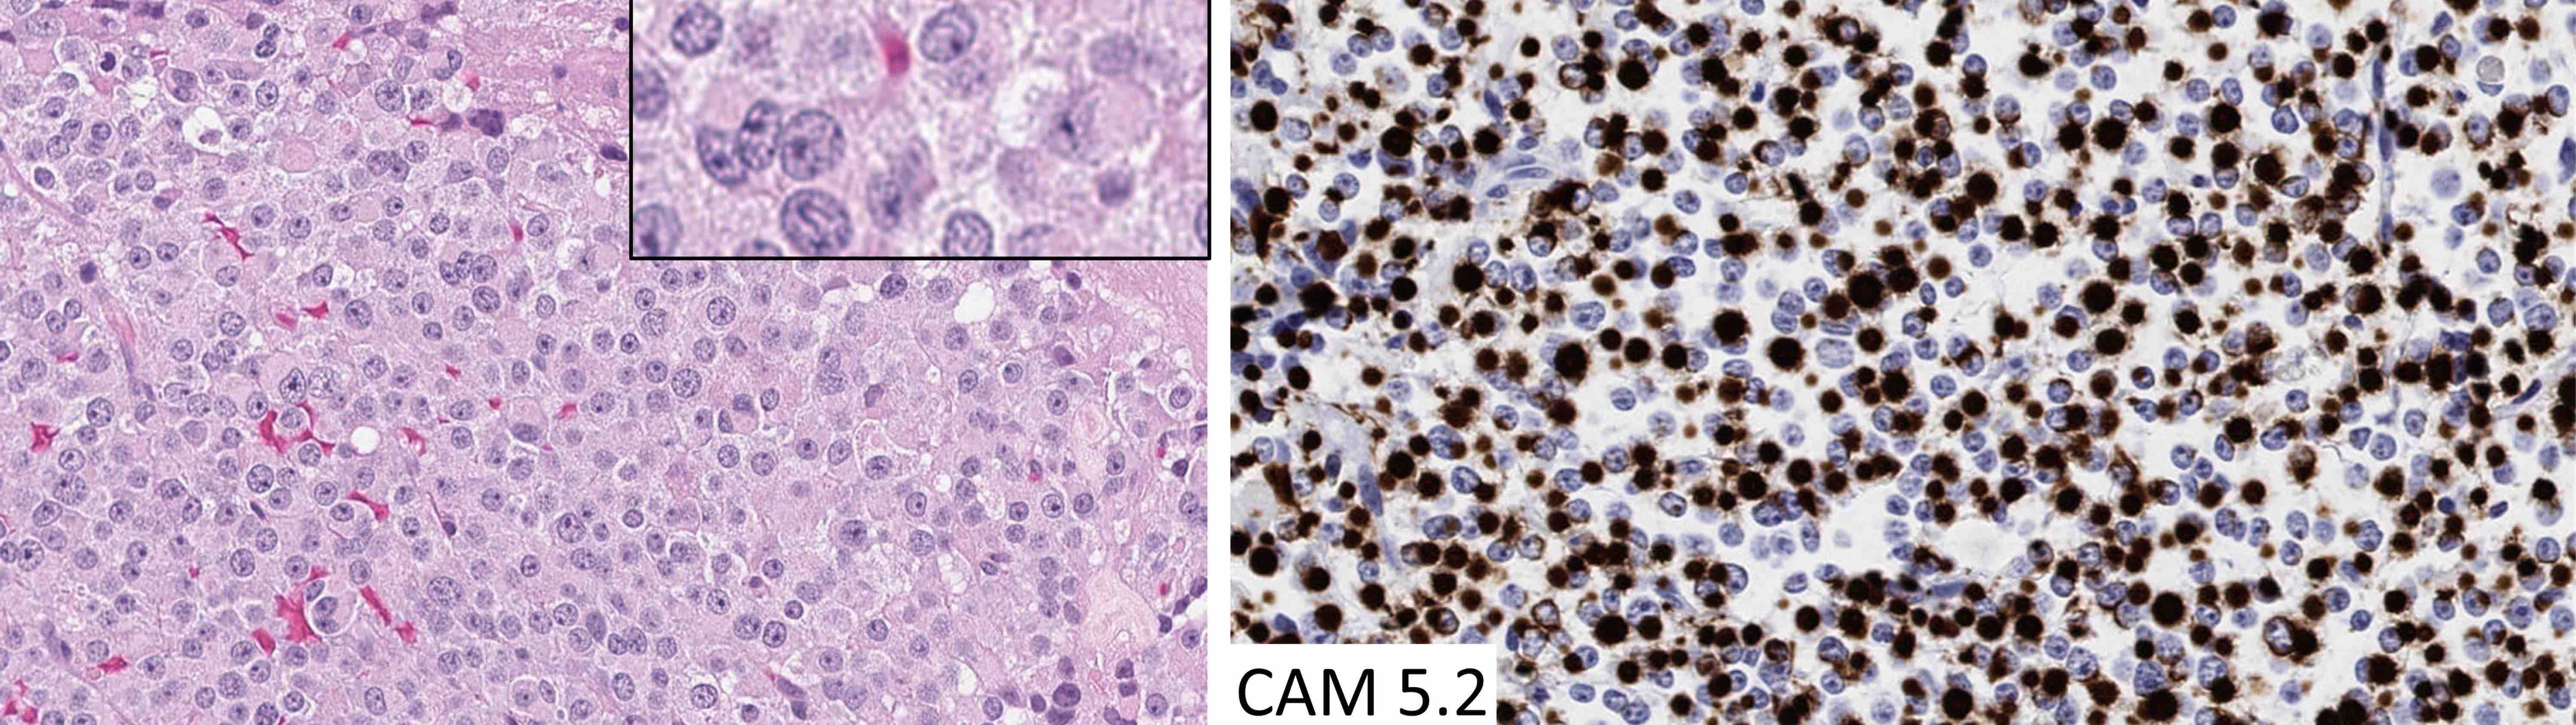

Contributed by Sylvia L. Asa, M.D., Ph.D.

Cytology description

- Normal pituitary has mixed cell types on smear preparation whereas tumors show uniform morphology and cell type

- Tumors produce cellular smear with discohesive small round blue cells

- Some tumors have specific cytologic atypia (e.g., fibrous bodies of sparsely granulated somatotroph tumors, Crooke hyaline of Crooke cell tumors)

- Paranuclear CAM 5.2 positive fibrous bodies are a conspicuous feature present in > 70% of tumor cells of sparsely granulated somatotroph tumors

The chromophobic tumor in the image above has the keratin pattern shown on the right. Which of the following is correct?

- This patient had acromegaly

- This patient had Cushing disease

- This patient would not have had hyperprolactinemia

- This tumor is likely to respond to first generation somatostatin analogues

- This tumor stains for Tpit

Practice answer #2

A. This patient had acromegaly. This sparsely granulated somatotroph tumor stains for Pit1 (not Tpit) and causes acromegaly, which may be associated with hyperprolactinemia due to the stalk section effect since sparsely granulated tumors are often large at the time of diagnosis. These tumors generally do not respond to first generation somatostatin analogues. Somatotroph tumors do not cause Cushing disease.